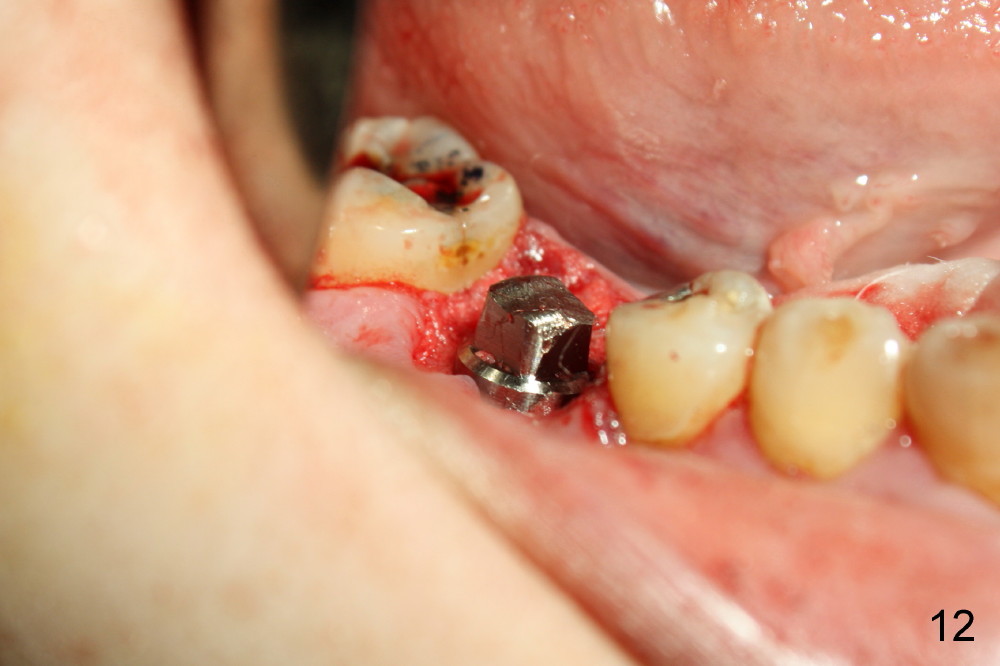

A 38-year-old lady agrees to have implant placement 7 years after loss of the crown of the lower right first molar (Fig.1,2). When the tooth is extracted, the septum is found to be low (Fig.3,4). To confirm it, a PA is taken (Fig.5). To initiate an osteotomy in the septum, it is trans-sectioned with thin osteotomes as shown in Fig.4 insert (black line). A 2 mm pilot drill is placed in the septum (Fig.6: P). The osteotomy is enlarged by 2.5-4.0 mm reamers (Fig.7,8), followed by insertion of 6x17 mm tapered tap at the depth 14 mm (Fig.9). The osteotomy is further enlarged by 4.5 and 5.0 mm reamers. A 6.0x14 mm one piece implant is placed initially. The trajectory is not ideal. A 6.0x14 mm one piece implant is placed initially. The trajectory is not ideal. The implant is removed from the osteotomy partially and reinserted with improved trajectory (Fig.11, compare to Fig.10 (red line)). Primary stability is high. There is not much bone mesiodistally so that the trajectory is easily changed in that direction. After abutment preparation, mixture of autogenous bone (harvested from reamers) and allograft is placed in the residual mesial and distal sockets (Fig.12). To contain the bone graft, an immediate provisional is placed (Fig.13 P). The occlusal plane of the provisional is significantly lower than that of the adjacent teeth to avoid micromovement of the implant. The patient is advised to eat soft food on the left side. Six days postop, the patient returns for prophy. The provisional is removed; the bone graft appears to be incorporating into the socket (Fig.14). After recementation, the provisional remains in place for 3.5 months; PA shows increased bone density in the mesial and distal sockets (Fig.15, compare to Fig.5,11). Due to insurance coverage, the patient defers fabrication of definitive restoration for at least 7 months. The immediate provisional is finally lost 8.5 months postop: the gingiva attaches to the 1-piece implant (Fig.16), while the density of the mesial socket increases (Fig.17 *) with formation of the cortex (lamina dura) coronally (v). Before the provisional (Fig.18 P) is removed for cementation of the definitive restoration, black shadow (*) is noted over the buccal gingiva. It is partially due to buccal placement (Fig.19) and partially due to buccal atrophy over a period of 10.5 months postop. How to prevent buccal placement? Positioning the first pilot drill in the septum buccolingually is a key. Eleven months post crown (Fig.20 C) cementation, the black shadow remains, but there is no tenderness. If the implant threads are immediately underneath the periosteum, there is tenderness.